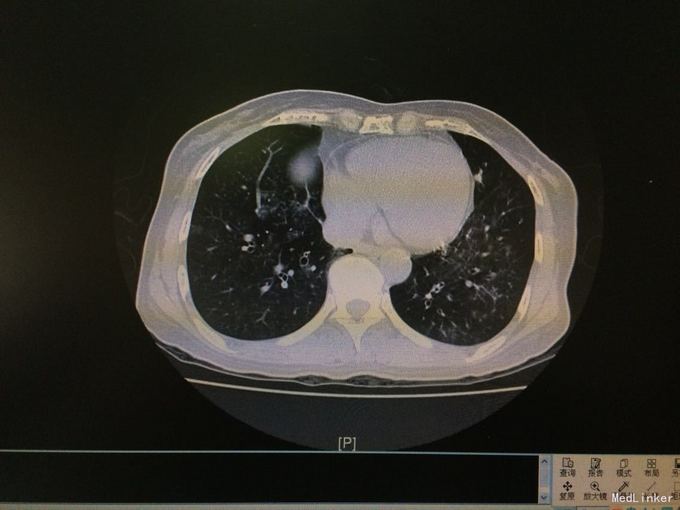

查体:双肺呼吸音粗,双肺底可闻及明显湿性啰音。 辅查:胸部CT示:双肺炎症。CRP66mg/l,ESR105mm/h,PCT0.074ng/ml。血常规、痰涂片及培养阴性。支气管镜示:左支气管见少量白色粘液状分泌物,右侧见中量白色脓性分泌物。支气管进管时患者无明显咽喉刺激反射。